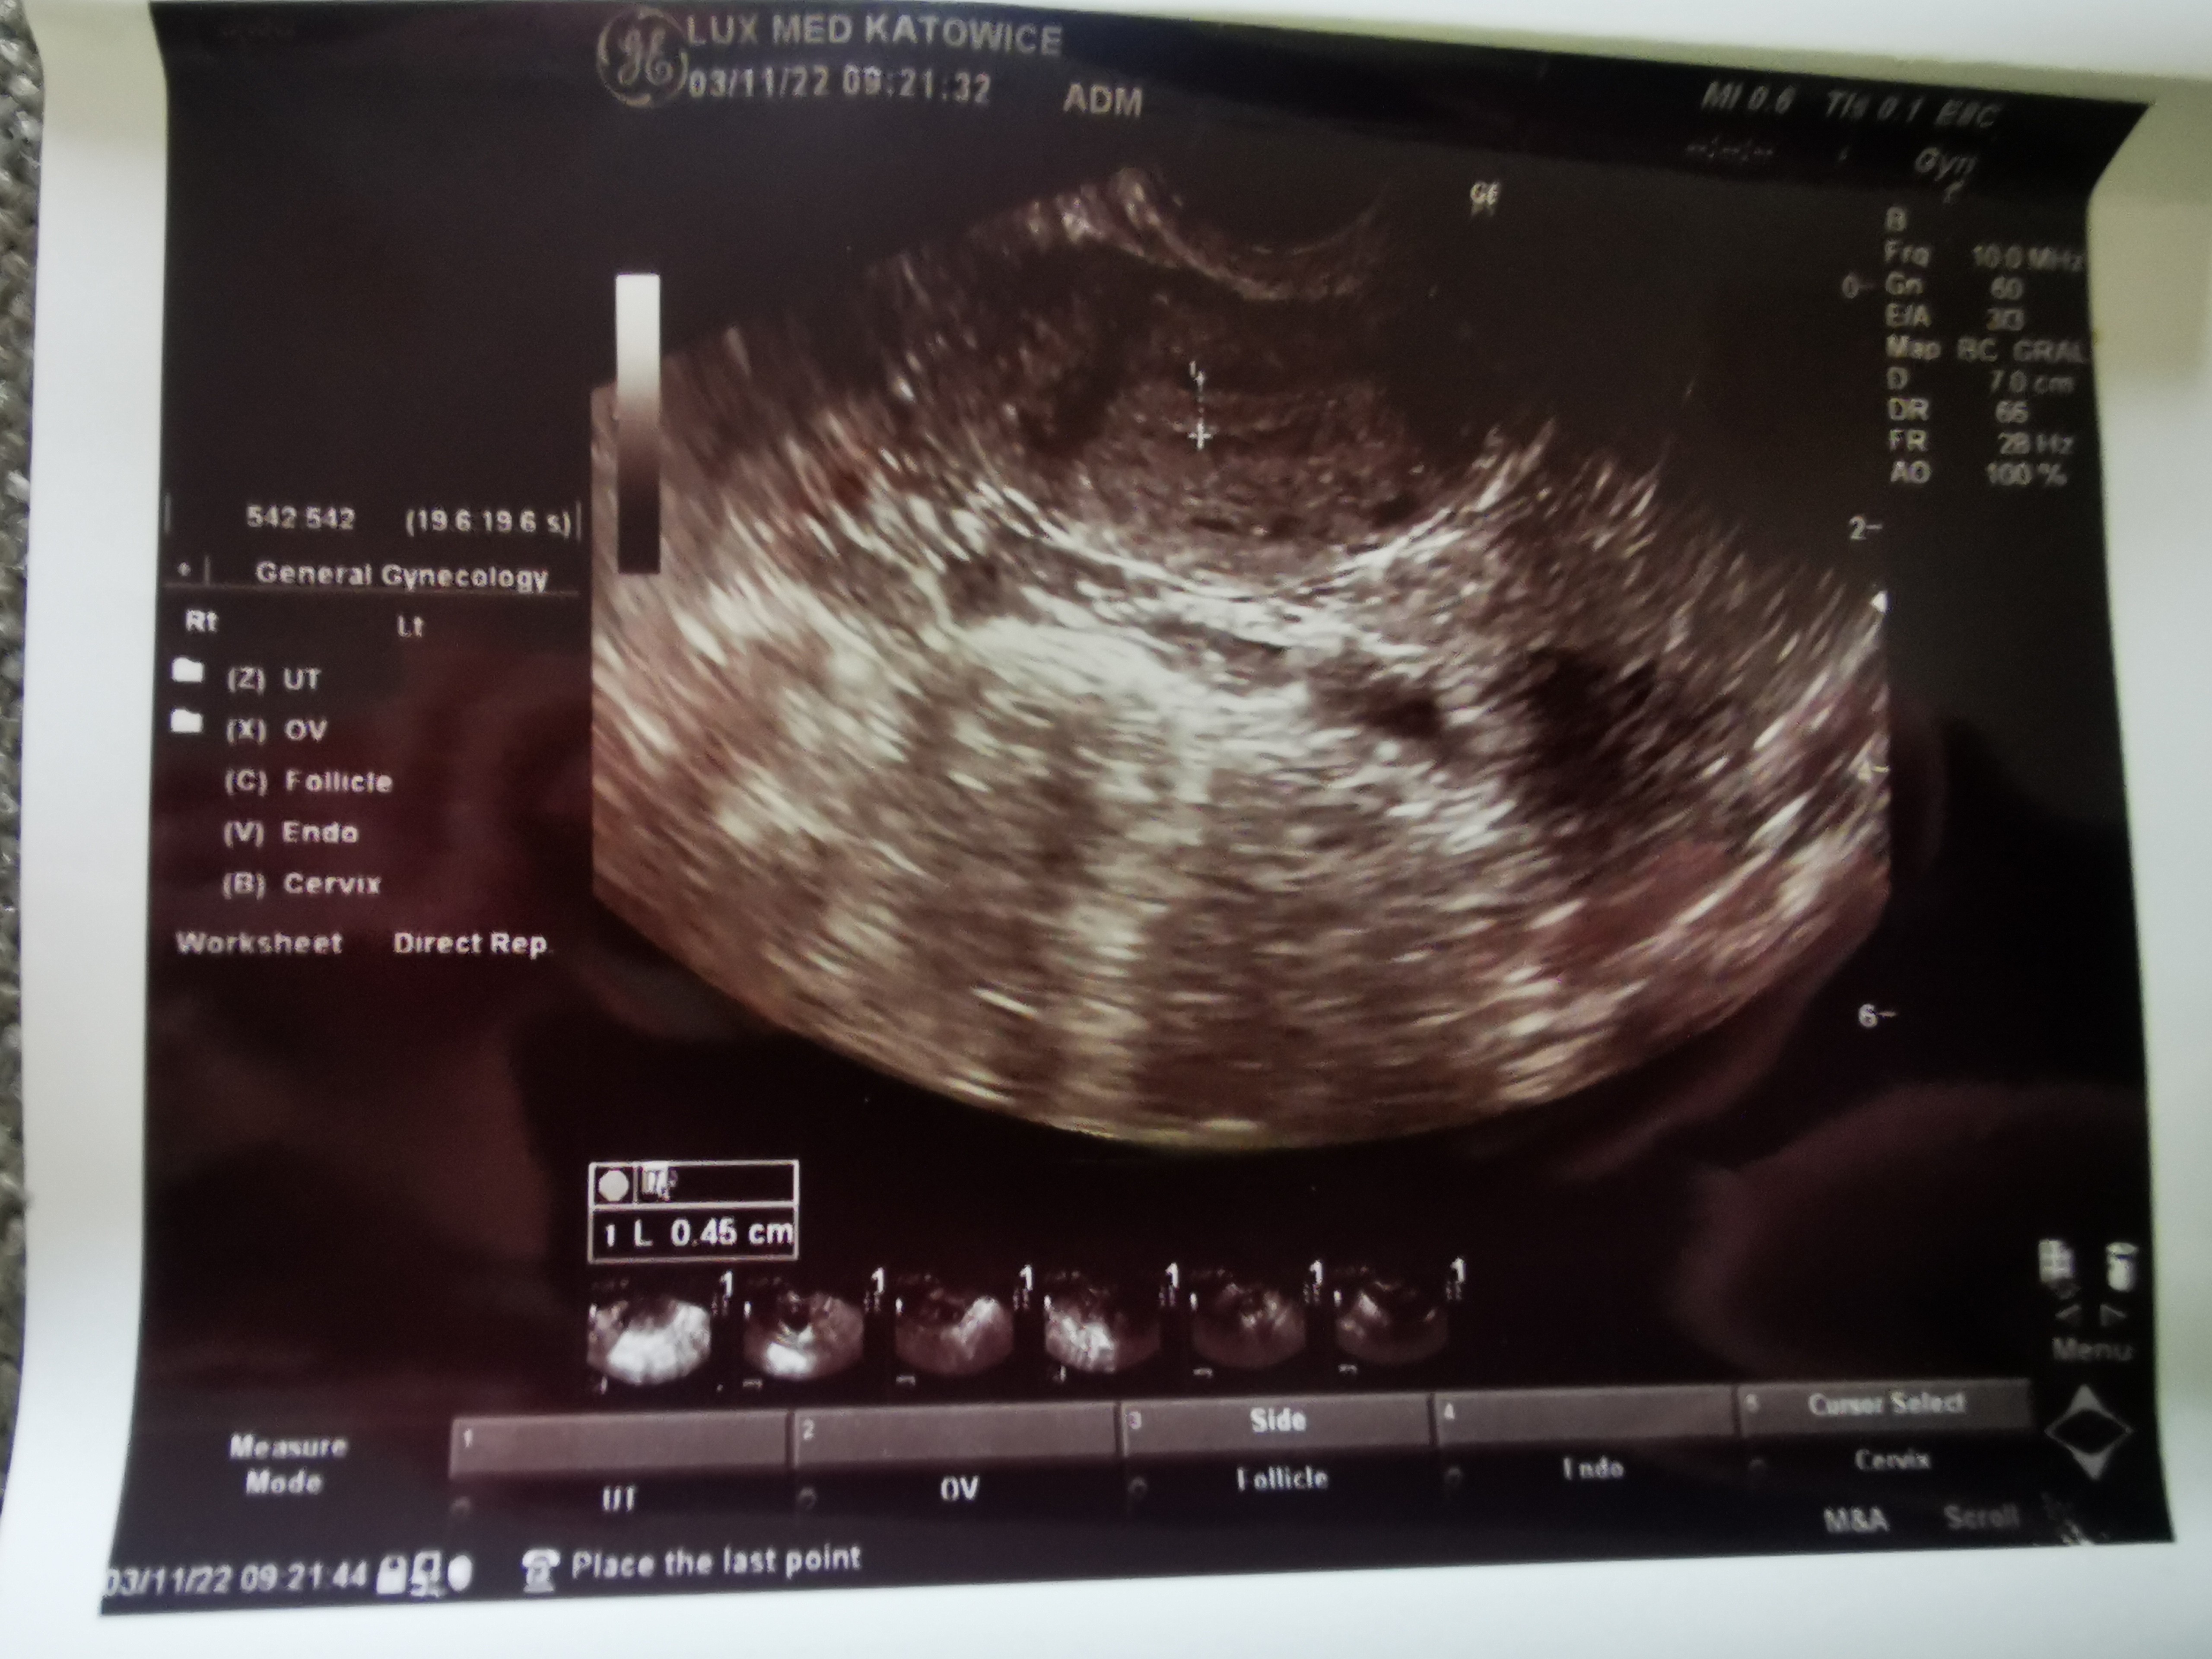

Zrobię jutro proga, bo jak badałam 3 listopada to był <0.1 i żadnych dominujących pęcherzyków.

Mam to trzymać do następnej wizyty 😂 to z 3 listopada. W ogóle nic nie kumam 😂🤷‍♀️, ale dla porównanie przy następnym monitoringu🤷‍♀️